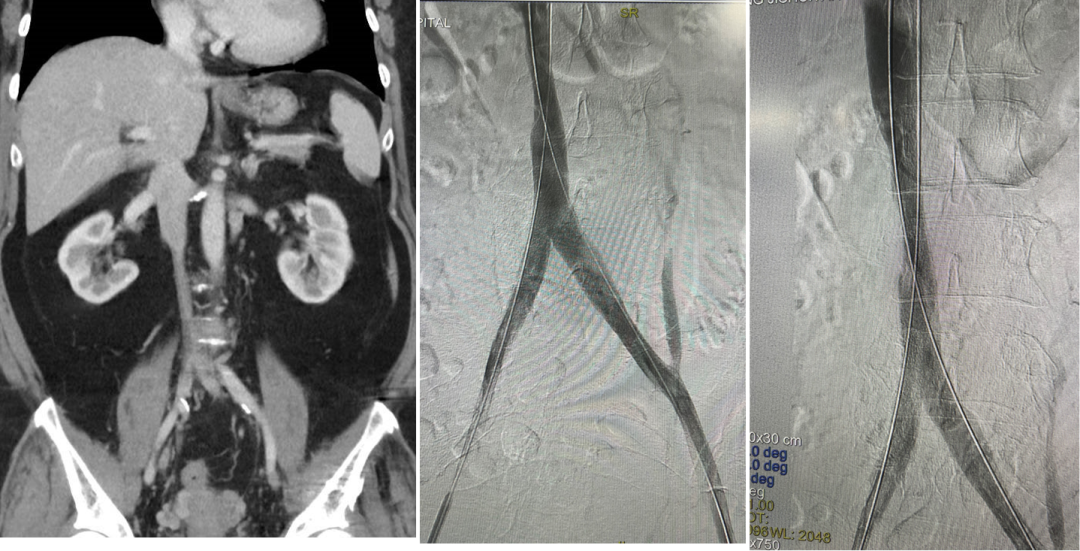

★ Case4:慢性IVCT腔髂静脉治疗

女,54岁

2024年10月22日坠落骨盆骨折,2024年11月7日置入下腔静脉滤器,11月8日手术。

2025年1月17日当地医院滤器取出术中发现下腔静脉髂静脉血栓放弃取出

图:第一次:扩张下腔静脉、髂静脉并取出滤器2025.2.13

图:二次复查CT并进行球囊扩张2025.3.31

图:早期复查结果比较满意(一年期通畅率>70%)